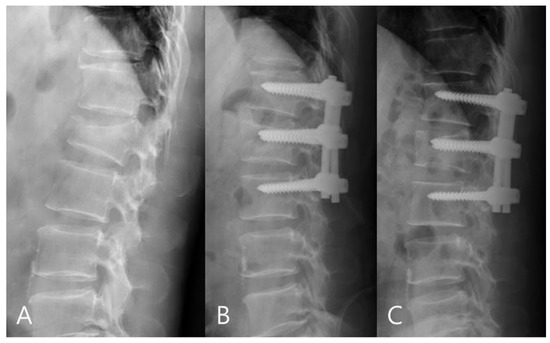

For the mono group, the preoperative mean RKA was 21.56°, and the postoperative mean RKA was 8.13°. The mean correction angle was 13.43° (correction rate 62.31%). The RKA angle decreased from 8.13° to 11.18° (correction loss: 14.18%) in late follow-up. For the poly group, the preoperative mean RKA was 23.18°, and the postoperative mean sagittal plane kyphosis was 11.09°. The mean correction angle was 12.09° (correction rate 52.17%).The RKA decreased from 11.09° to 18.83° (correction loss: 33.42%) in late follow-up. The mono-axial pedicle screw fixation had a better correction rate and reduced the risks of correction loss versus the poly-axial pedicle screw fixation (Figure 3 and Figure 4).

Figure 4.

(A) 45-year-old male patient with L1 burst fracture was treated by poly-axial pedicle screw fixation. (B) Postoperative imaging showed a mild correction of anterior body height and kyphosis. (C) Final follow-up imaging showed correction loss.